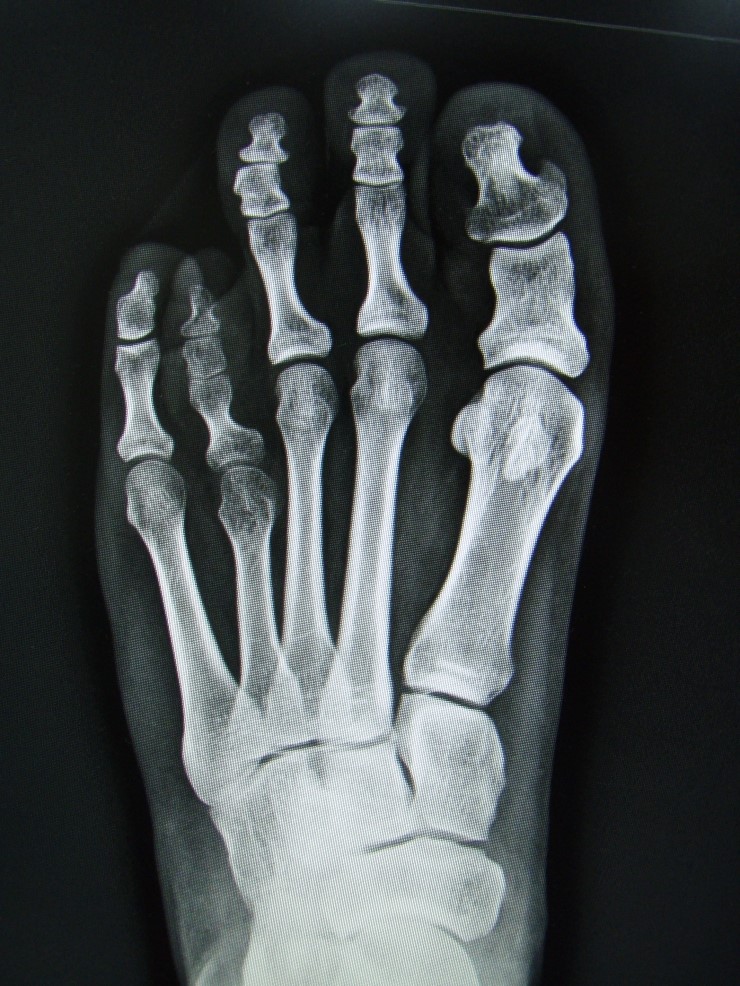

중족골이 비정상적으로 자라나고 뼈가 자라야 할 만큼 자라지 않아 발가락 길이가 짧아 보입니다.

합병증은 주로 네 번째 발가락에 발생하며 짧은 엄지발가락이 흔하며 여성에게 더 흔하다. 발가락 모양에 문제가 있는 경우 수술을 고려할 수 있습니다.

다식증은 수술로 교정이 가능하며, 자가골이식술을 이용하여 발가락을 늘려줍니다 절골술 후 골반뼈의 일부를 절제하여 다형성 중족골을 이식하는 방법입니다. 절골술과 뼈이식술이 있으며, 수술을 위해서는 약 5-7일 정도 입원하게 되며, 수술 후 6주까지는 깁스로 발을 보호하게 됩니다. 일반 신발을 신으면 정상적으로 걷는 데 평균 2~3개월이 걸립니다.